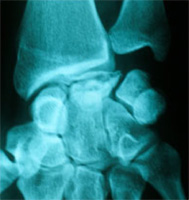

La rhizarthose c’est l’arthrose de la base du pouce. Elle atteint l’articulation entre le trapèze et le premier métacarpien. C’est un problème fréquent qui atteint particulièrement les femmes de la cinquantaine et souvent des 2 côtés à des stades cliniques et radiologiques différents. Parfois l’arthrose est la conséquence d’une fracture, d’un rhumatisme ou d’une infection. Mais le plus souvent la cause exacte de l’arthrose n’est pas connue. Elle est dite idiopathique.

Le symptôme habituel est la douleur, particulièrement dans les gestes de la vie quotidienne utilisant la pince pollici-digitale (c’est-à-dire le pouce avec un autre doigt) comme tourner une clé, ouvrir un bocal, ouvrir une fenêtre. Peu à peu, l’articulation se détériore puis se sub-luxe et apparaît alors une déformation caractéristique à la base du pouce.

Les radiographies de face et de profil du pouce (incidence de Kapandji) permettent de confirmer le diagnostic clinique et d’apprécier l’importance de la destruction articulaire et la conservation d’un certain volume osseux.